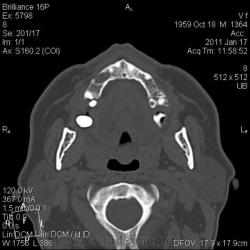

КТ головного мозга. Случайная находка. Жалоб "на челюсти" нет.

Мужчине 51 год. Периферический рак легкого. Очаговых изменений головного мозга не нашла. Пациент не критичен к своему состоянию (никуда не поеду, пусть как есть остается), поэтому отсутствие жалоб еще ничего не значит.

Контуры внутренние деструктивной полости изъеденные, кость вздута, но внешне не видно. В центре уровень?  с плотностью 30 ед.Н. Адамантинома? С зубными делами практически не сталкиваюсь. Нужна Ваша помощь. Какие будут идеи, уважаемые коллеги?

Конечно, одно другому не мешает... Написала адамантиному под вопросом, рекомендовала консультацию стоматолога. На мтс вроде не очень похоже, на остеомиелит - тоже.  Мягкотканного компонента - нуль. Как найду что-нибудь... и с большими глазами сюда)).

На мой взгляд процесс был, да прошел. Состояние после апикальной кисты удаленного зуба

Я думаю, это радикулярная киста с вторичным гиперостозом стенок воспалительного характера. Не уверен, что это состояние можно назвать остеомиелитом.

На метастаз и адамантиному непохоже.

До кабинета стоматолога дело не дошло. Просто триллер получился... пациент отказался от осмотра, мол, выписывают, как заболит - пойду в поликлинику. А когда пришел за диском с DICOM, у меня в ординаторской была стоматолог. Ей-богу случайно!)) Осмотрели ротовую полость. Хоромlaugh. Слизистая совершенно нормальная. Потом мы тем же хором его анамнестически "пытали" - каждое слово вытягивая словно клещами. Затащить в стомат.кресло не удалось, но вывод стоматолога после просмотра КТ таков - вероятнее всего, киста с периодическим нагноением.